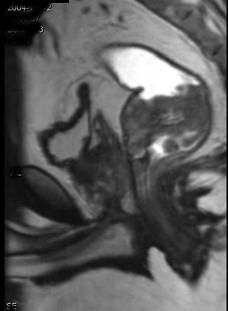

问题 男,70岁,下腹部腹胀、腹痛、排便困难,逐渐加重,MRI示直肠内不规则充盈缺损,请选择最佳诊断结果 ( )

选项 A.直肠息肉 B.直肠癌 C.直肠间质瘤 D.直肠转移瘤 E.直肠淋巴瘤

答案 B